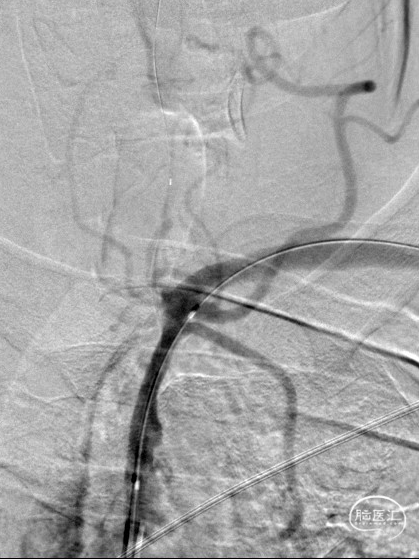

DSA:LSub。

DSA:L-CCA。

0.018*300cm 外周导丝至左肱动脉,0.014*200cm 通桥北斗SS™神经血管导丝超选至左椎V2段远端。

沿0.018*300cm 外周导丝送入6*40 外周球囊送至左侧锁骨下动脉狭窄处,压力泵逐渐加压到6atm。

撤出球囊后见残余狭窄40%。

再次沿0.018*300cm 外周导丝送入6*40 外周球囊达LSub狭窄部位,压力泵逐渐加压到8atm,见残余狭窄20%。